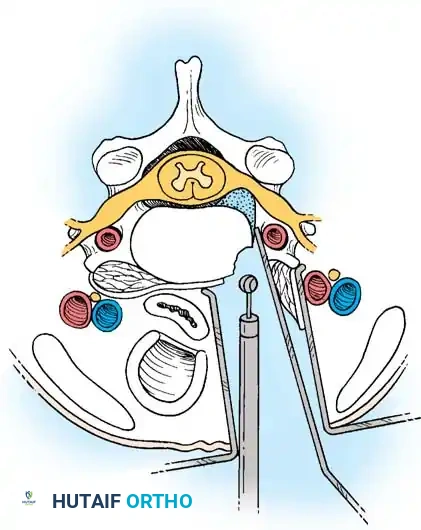

Step 2: Annulotomy and Discectomy

Self-retaining retractors are placed beneath the elevated medial borders of the longus colli. A rectangular annulotomy is performed using a #11 blade. The disc material is systematically removed using pituitary rongeurs and curettes.

Step 3: Decompression

The posterior longitudinal ligament (PLL) is carefully identified and often resected to ensure no extruded disc fragments remain in the epidural space. High-speed burrs and Kerrison rongeurs are utilized to resect posterior osteophytes and decompress the uncinate processes bilaterally, ensuring the exiting nerve roots are entirely free.